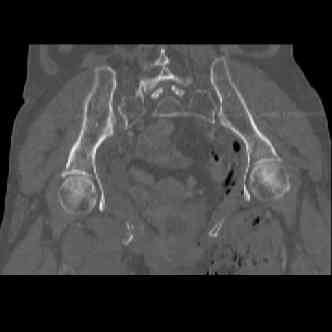

attached are several CT cuts. please let me know if you need more. the CT is pre-pelvic ex-fix placement.

injuries are limited to the pelvis. left rami open and visible in a 10cm vertical laceration just lateral to left labia majora. wound is grossly clean. no vaginal and no urinary issues. CT scan shows widening of both SI joints anteriorly but I think this is vertically stable pattern.

so the question is what next operatively if anything? concerns are infection, nonunion anteriorly and possible incompetence of the pelvic floor which may lead to prolapse issues. right rami are comminuted and plating may entail ilioinguinal approach to extend plate laterally to right iliac wing. retrograde screw up right rami is an option but I am not convinced it will add much. adding SI screws very doable, but major concern is restoring anterior ring. so far wound is clean and closed over a drain, and I have no plans to open it back up and wash again.

I wouldn't plate the front.

But I would add screws posteriorly.